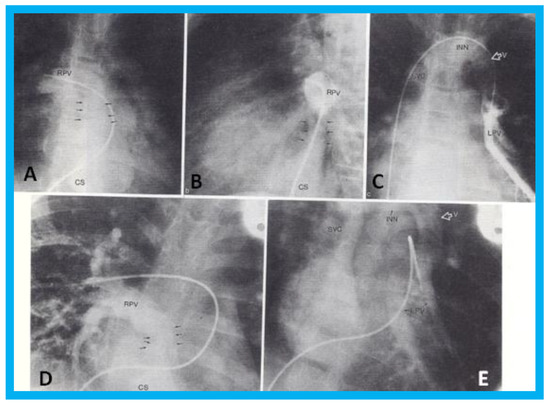

Transthoracic echocardiogram in case 1 showed dilated right atrium (RA) and right ventricle (RV) with a common pulmonary venous confluence (Figure 6a) and a vertical vein emptying into the innominate vein and superior vena cava (SVC) (Figure 6b,c). Dilated coronary sinus (CS) with mosaic color-Doppler flow pattern of pulmonary venous entry was also seen (Figure 6d,e). These findings indicated mixed type of total anomalous pulmonary venous connection. The findings in case 2 were very similar to those seen in case 1. However, not all pulmonary veins were identified and their course and connections to the pulmonary venous confluence could not be established. Therefore, catheterization and cineangiography were undertaken to validate the diagnosis prior to corrective cardiac surgery. Levo-angiographic frames following right pulmonary artery cineangiogram demonstrated entry of right pulmonary veins into the coronary sinus in both cases (Figure 7a,b,d). Direct injection into the left pulmonary vein via a catheter positioned into it via the innominate and vertical veins in the first case (Figure 7c) and on levo-angiogram following left pulmonary artery cineangiogram in the second case (Figure 7e) clearly demonstrated left pulmonary venous drainage via the vertical vein into the systemic venous circuit. Transesophageal echocardiography during surgery in both cases could not delineate the number of pulmonary veins and their connection with the confluence, although we had only access to single-plane TEE probe at that time.

Figure 6. Selected two-dimensional (a) and color flow images (be) of a patient (case 1) with mixed type of total anomalous pulmonary venous connection are shown. In (a), dilated right atrium (RA) and right ventricle (RV) and common pulmonary venous confluence (CC) are illustrated. In (b,c), spectral and color flow images demonstrate the vertical vein draining into the innominate vein and superior vena cava (SVC). In (d,e), dilated coronary sinus (CS) with mosaic color flow pattern of pulmonary venous entry are apparent. ARCH, aortic arch; LA, left atrium; LV, left ventricle. Reproduced from Reddy S.C.B., et al. [8].

Figure 7. Selected cineangiographic frames from postero-anterior (A,D,E) and lateral (B,C) views of case 1 (AC) and case 2 (D,E) demonstrating mixed total anomalous pulmonary venous connection. In (A,B), levo-angiographic frames following right pulmonary artery cineangiogram demonstrated entry of right pulmonary vein (RPV) into the coronary sinus (CS) in case 1. In (C) is the selected angiographic frame from left pulmonary vein (LPV) cineangiogram demonstrating pulmonary venous drainage into the vertical vein (V) and then into the innominate vein (INN) and superior vena cava (SVC), also of case 1. In (D), levo-angiographic frame following right pulmonary artery cineangiogram demonstrating entry of right pulmonary vein (RPV) into the coronary sinus (CS) in case 2 is shown. In (E), levo-angiographic frame following left pulmonary artery cineangiogram demonstrating drainage of left pulmonary veins (LPV) into the vertical vein (V) and then into the INN and SVC of case 2 is shown. In (A,B,D), the connections of the RPVs to the CS are marked with arrows to improve clarity. Reproduced from Reddy S.C.B., et al. [9].